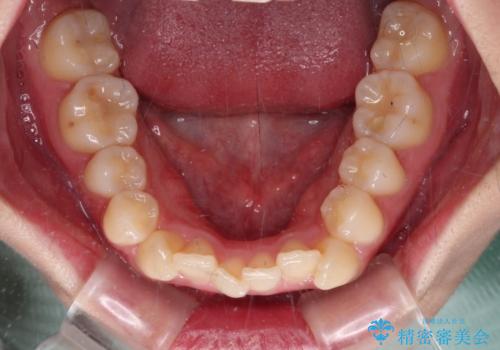

- 八重歯やクロスバイトを気にして来院された患者様です。

口元の突出感はありませんでしたが、デコボコが強く、非抜歯矯正とすると出っ歯仕上がりとなる可能性があったため、上下左右の第一小臼歯4本を抜歯し、ワイヤー装置にて矯正治療を行うこととしました。